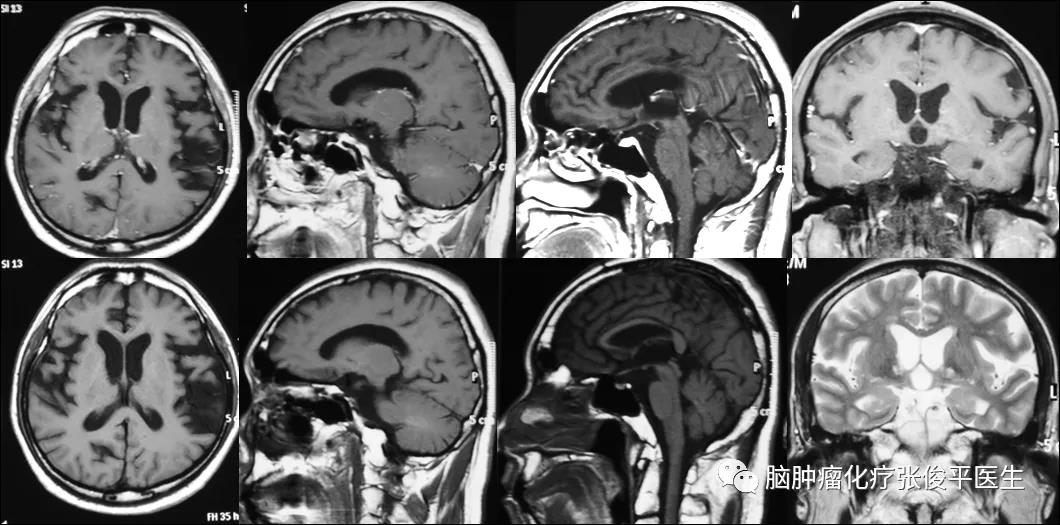

患者共化疗6个周期,末次化疗日期为2010年11月30日。化疗结束后1个月复查核磁,未见肿瘤复发(如图3)。

图3. 2011-01-06核磁,6周期化疗结束后1个月,未见肿瘤复发征象。

2011-4-18,在化疗结束后3个月,患者接受全脑放疗19次。之后定期复查。最近一次复查是2020-8-7,距离发现肿瘤已10年余,复查核磁未见肿瘤复发(图4),患者正常上班,无任何不适症状;喜欢游泳,每次可游2千米;记忆力好,曾参加当地党员知识竞赛获得一等奖。

图4. 2020-8-7核磁,随访10年后,未见肿瘤复发。